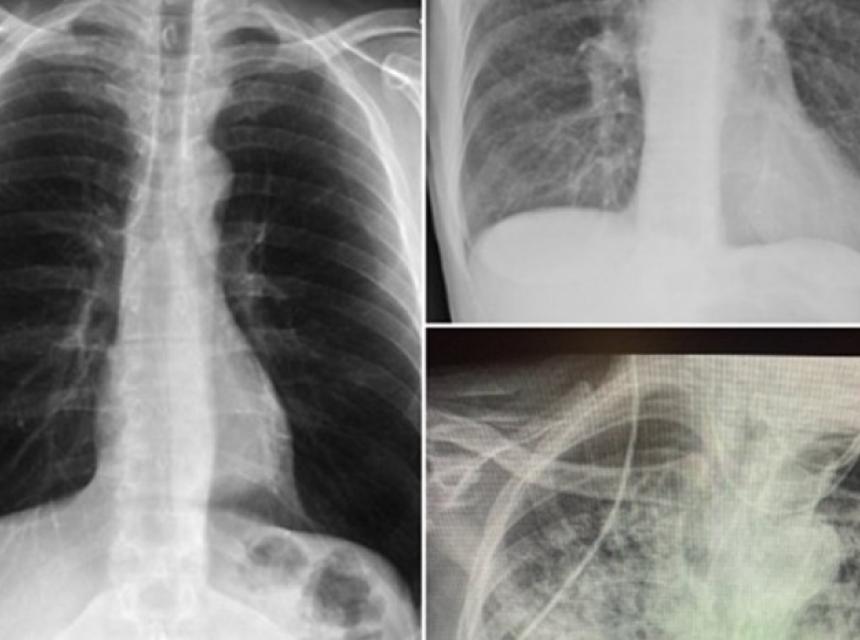

Naime, ona je na svom Twitter profilu podijelila tri rendgenske snimke pluća: jednog zdravog pacijenta, jednog pušača i jednog pacijenta koji je prebolio koronavirus.

Rendgenski snimci

- Ne znam tko ovo treba vidjeti, ali pluća nakon Covida izgledaju gore od bilo koje vrste pluća pušača koju smo ikad vidjeli. I ona se urušavaju. I zgrušavaju. I otežano disanje se zadržava... i dalje ... i dalje - napisala je uz rendgenske snimke.

Snimka pluća zdravog pacijenta je bistra jer imaju puno crnog prostora, što ukazuje na to da osoba može udahnuti puno zraka. Gledajući rendgen pluća pušača, primjetna je maglovitost koja ukazuje na ožiljke i začepljenja. Treća slika prikazuje pluća nakon Covida, koja izgledaju gotovo potpuno bijelo, što znači da su pluća ozbiljno oštećena. Nakon što je njezin tvit dobio puno pažnje i hiljade odgovora, doktorica je pozvana da kaže nekoliko riječi u vijestima na CBS-u.